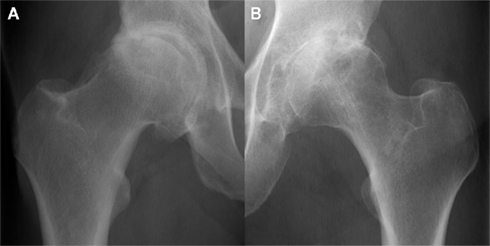

- Fase Attiva: necrosi del tessuto cartilagineo, buchi nel tessuto cartilagineo, “come in un formaggio svizzero”.

- Fase Pcl: iperplasia del tessuto cartilagineo, ipercondrosi

Nella totalità degli interventi di artroprotesi d'anca, la condizione delle cartilagini è disastrosa. Hanno subito così tante attivazioni e rimaneggiamenti che lo strato cartilagineo è pressoché scomparso, sostituito da tessuto fibroso di grande durezza. Nel momento della alesatura (ovvero regolarizzazione della superficie articolare) le frese taglienti impiegate per la rimozione dello strato fibroso, incontrano grandi difficoltà nell'eseguire l'azione abrasiva. Il chirurgo è costretto ad applicare grandi pressioni e ripetuti tentativi per rimuovere la "lastra" di tessuto. È talora richiesto l'uso di scalpelli e martello per rendere la superficie lavorabile. Talora il motore del trapano si blocca per l'intensissimo sforzo.

Data la pressoché totale asportazione della cartilagine articolare, è improbabile che questa possa essere l'origine di una infezione post-chirurgica.